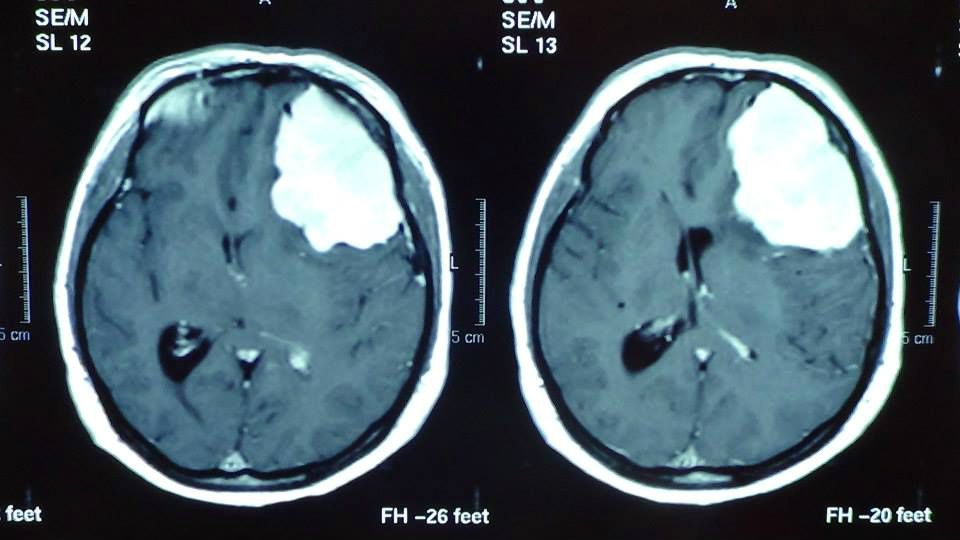

Perioperative cerebral stem (fourth ventricle territory) coronary angioma

Total removal of the angioma with the patient neurologically intact.